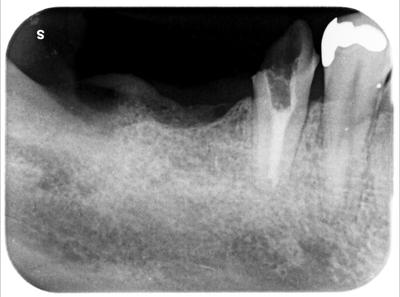

右下痛みにて来院。

右下5部を前医にて根管治療行ったらしいが、状況改善せず抜歯宣告受けての当院へ相談。

状態の悪い右下7部ならびに6欠損部についての説明はなし。

右下7部は歯根周囲に全く骨が存在せずグラグラの状態、歯根破折も認めたため残念ながら抜歯。

右下5部は精度の低い根管治療が行われていたため、再度根管治療行った。

根管充填はMTA使用。(保険診療適応外)